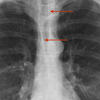

Paratracheal stripe